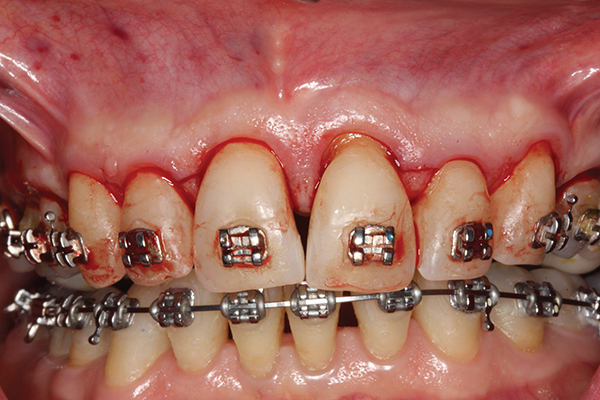

Fig 1. Preoperative SFOT. No loss of attachment, but thin dentoalveolar bone phenotype noted clinically.

Figure 1